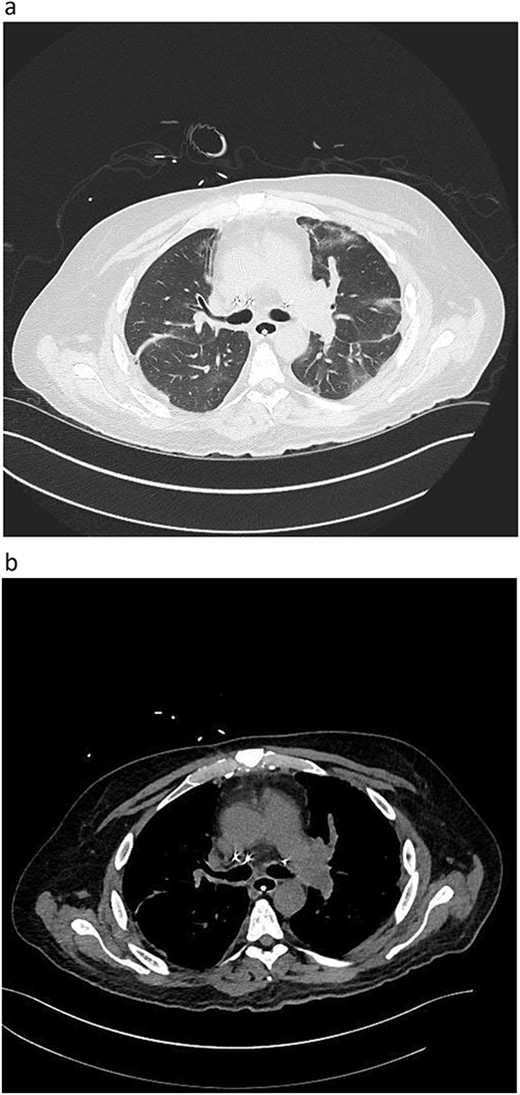

During back-table preparation at the recipient hospital, a large partially adherent thrombus was observed in the LPA, suggesting a subacute process. We gently peeled and removed a 10-cm thrombus from the LPA wall (Fig. 3). Because we were unsure whether more thrombi were present in the left lung, we performed thrombolysis by injecting 4 mg of recombinant tPA (alteplase) into the LPA and let it dwell for 10 min before a second retrograde flush with 2 L of PERFADEX Plus (XVIVO) solution, which removed many more clots. Bilateral sequential lung transplant was performed in a 50-year-old female recipient who was on extracorporeal membrane oxygenation because of COVID-19–associated pneumonia. After transplant, she was weaned from extracorporeal membrane oxygenation and had an uneventful recovery. She was discharged 30 days after transplant (Fig. 2).

Postoperative graft CT scan: recipients had bilateral lung reduction due to over size.